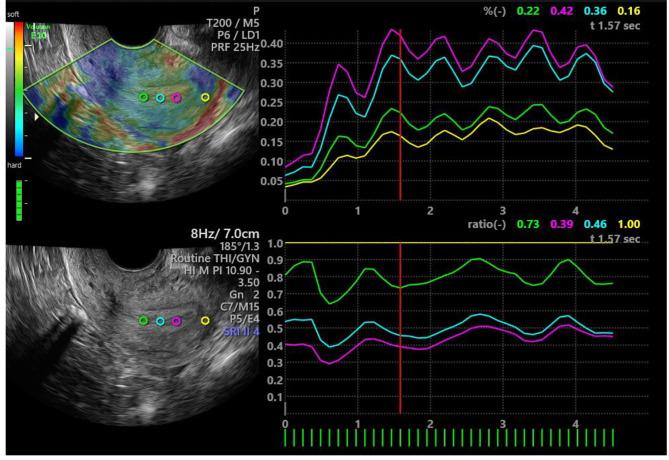

Three hundred and twenty normal women were recruited at our hospitals from November 2021 to December 2022. Each volunteer underwent a transvaginal two-dimensional (2D) and SE ultrasound during either the endometrial proliferative or secretory phase. The 2D ultrasound indices obtained included endometrial thickness, echo type (type A, B, and C), and blood flow grading (grades 0, 1, 2, and 3). SE indices obtained included endometrial strain values, myometrial strain values, and endometrial strain ratios. Differences in endometrial ultrasound indices between different menstrual cycles and different age groups were compared.

Comparison of 2D ultrasound parameters revealed that endometrial thickness in the proliferative phase endometrium group was smaller than that in the secretory phase endometrium group, with a statistically significant difference. Additionally, there was a statistically significant difference in endometrial echo types between the two groups, while the disparity in endometrial blood flow grading was not significant. Regarding SE parameters, the median and mean values of endometrial strain ratio in the proliferative phase endometrium group were smaller than those in the secretory phase endometrium group, showing a statistically significant difference. However, there were no significant differences observed between the two groups in endometrial strain and myometrial strain in the fundus. Furthermore, there were no significant differences in any of the endometrial ultrasound indices among the different age groups.